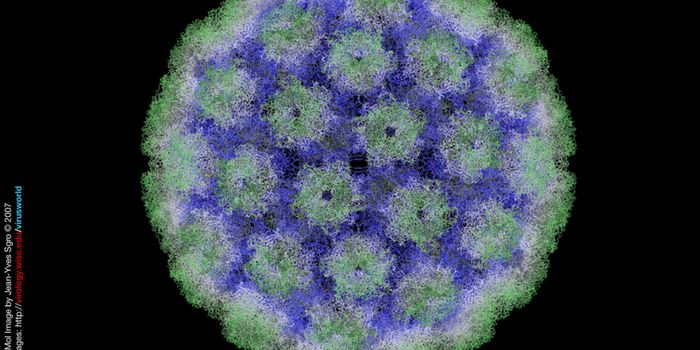

APR 25, 2016ImmunologyA new vaccine for human papillomavirus (HPV) would significantly reduce both cervical cancer incidence and health care c ...